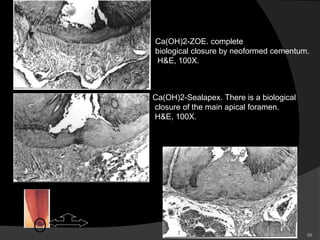

Ca(OH)2-ZOE. complete

biological closure by neoformed cementum.

H&E, 100X.

Ca(OH)2-Sealapex. There is a biological

closure of the main apical foramen.